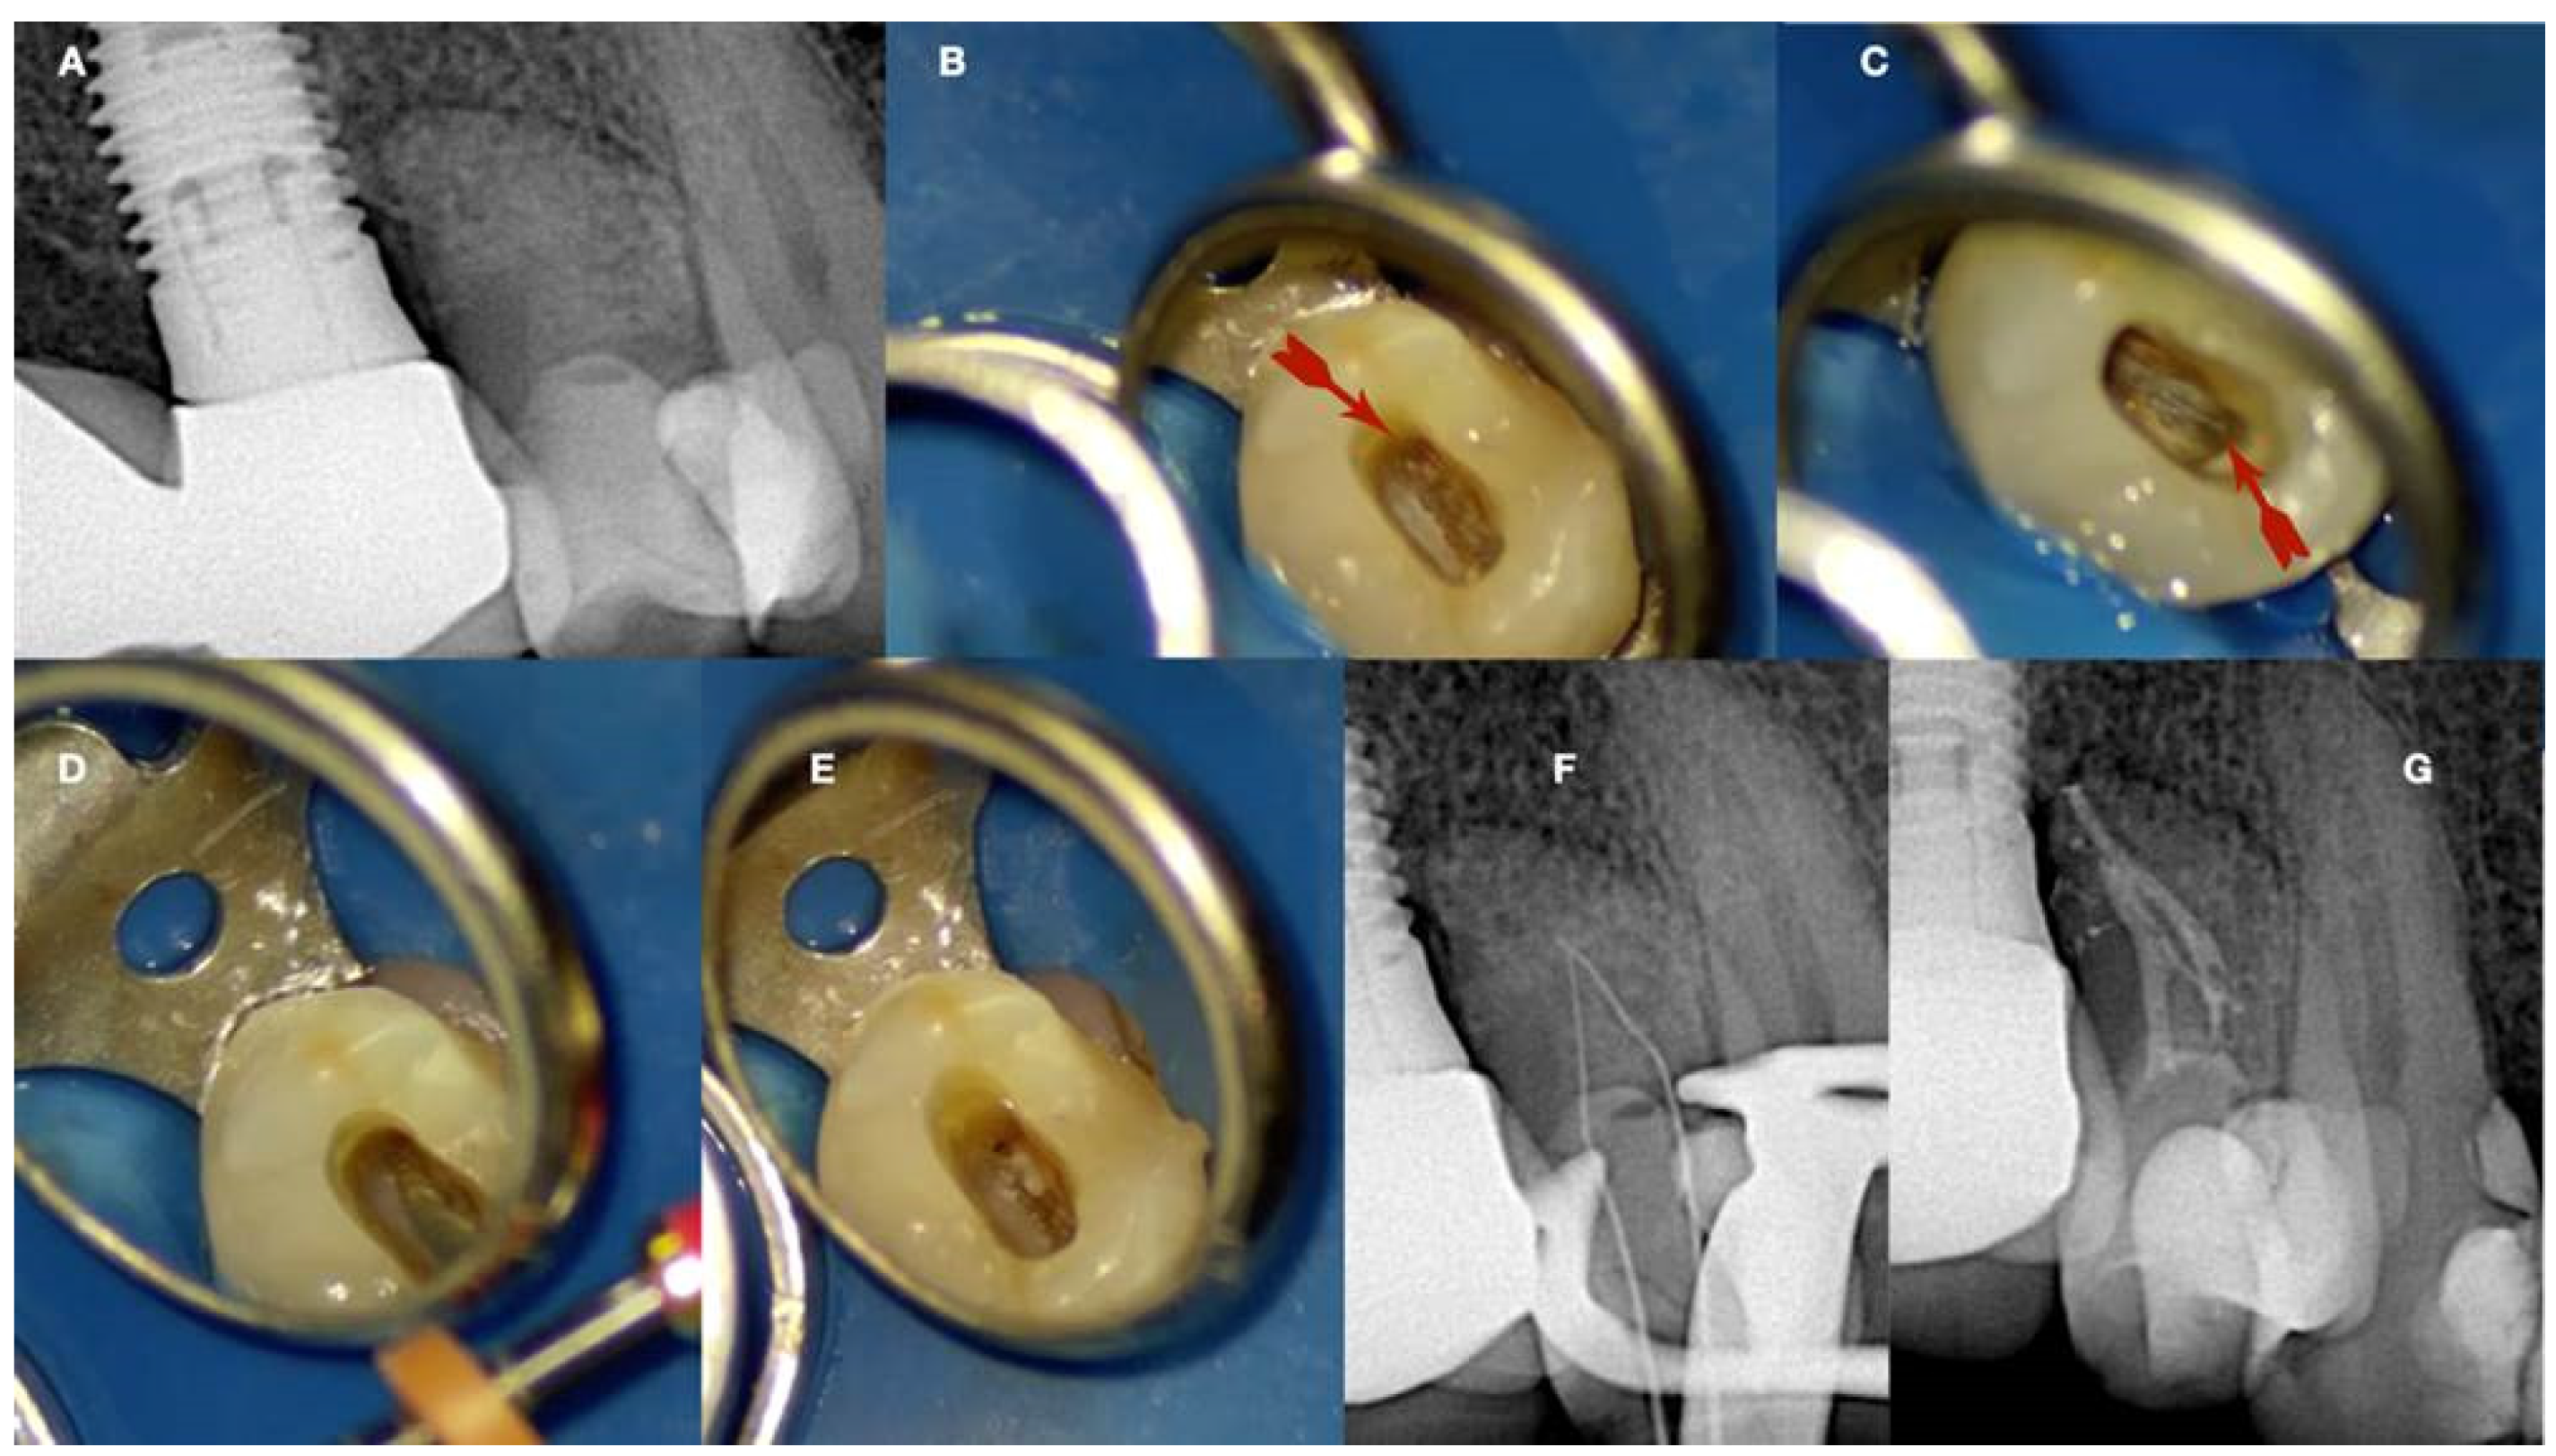

Figure 12.

Calcified maxillary molar negotiation (A). Preoperative radiograph of the maxillary molar with no detectable canals (B). A clinical view of the access cavity reveals a completely calcified chamber (C). Clinical view of the ultrasonic troughing of the pulp floor. Notice that the pulp floor color is grey (D). Clinical view of the axial wall floor junction developmental line (yellow arrow). The canal entrances in a maxillary molar always originate from this line (E–G). Clinical image of the shaped canals. Notice that the location of the canals in a calcified maxillary molar is always lying along the wall–floor junction developmental lines (H). Postoperative radiograph of the calcified maxillary molar treatment (clinical images and radiographs courtesy of Dr. Chaniotis Antonis).

Figure 13.

Calcified mandibular molar negotiation (A). Preoperative radiograph of a calcified mandibular molar with no visible canals (B). Clinical view of the calcified chamber (C). Clinical view of the calcified tissue blocking the access to the mesial canal system. Notice the white color of the calcification. The axial walls are yellow, and the pulp floor is always grey (D). Clinical view of the pulp floor developmental lines after the removal of the white calcified tissue. Chasing the dark grey developmental lines to their termini will reveal the calcified canal entrances (E). Clinical view of the canals shaped (F). Postoperative radiograph of the calcified mandibular molar canal treatment (clinical images and radiographs courtesy of Dr. Chaniotis Antonis). Black arrow: calcified structure covering the canal orifices and the developmental pulp chamber lines, red arrows indicate the canal orifices after the removal of the white calcified structure (black arrow).

Figure 14.

Calcified maxillary premolar negotiation (A). Preoperative radiograph of a calcified maxillary premolar associated with apical periodontitis (B). Clinical view of the palatal calcified canal orifice (red arrow) (C). Clinical view of the buccal calcified canal orifice after chasing the pulp floor developmental line to its far end (red arrow) (D). Clinical view of the EDM file buckling resistance activation test negotiation (E,F). Clinical and radiographic images of the calcified canal negotiation, (G) postoperative radiograph of the calcified maxillary premolar treatment (clinical images and radiographs are courtesy of Dr. Chaniotis Antonis).